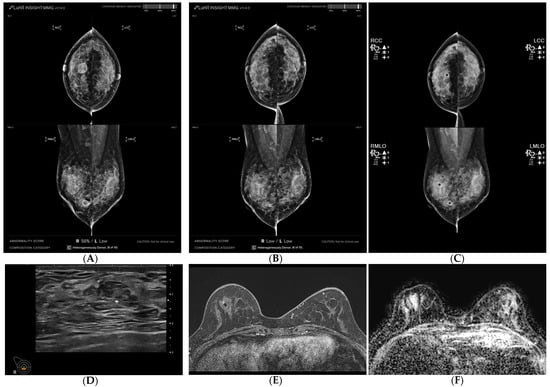

Figure 1. A 54-year-old woman diagnosed with breast cancer presenting as a mass with calcifications, exhibiting a surgically confirmed pathologic complete response (pCR) following neoadjuvant chemotherapy (NAC). (A,B) Mammography was analyzed using AI-CAD, identifying an area in the left central breast of a mass with calcifications in pre-NAC images (AI-CAD score 98% on the MLO view), and no mark was detected in post-NAC images. (C) Utilizing conventional CAD, identifying an area in the left central breast corresponding to the calcifications in post-NAC images. (D) Post-NAC ultrasound recorded a reduction in mass size from 26 mm. (E) Post-NAC maximal intensity projection (MIP) of contrast-enhanced MRI (CE-MRI) documented a mass reduction from 36 mm. (F) Post-NAC ADC map of DWI displayed regression of the mass.